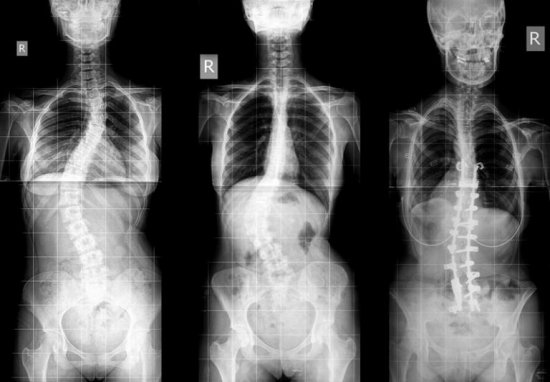

С помощью рентгенографии позвоночника можно определить степень поражения, место локализации деформации и очаги воспаления. Рентгенография использует в основе радиоактивное излучение, поэтому беременные женщины и маленькие дети не могут проходить данную диагностику

При заболеваниях, вызванных деформацией структур позвоночника, доктор назначает рентгенография или МРТ. Именно эти методики дают четкое представление об анатомическом изменении костных структур позвоночного столба. Трехмерное изображение срезков костной ткани предоставляет медицинскому работнику полную картину болезни, после чего он может точно назвать диагноз.